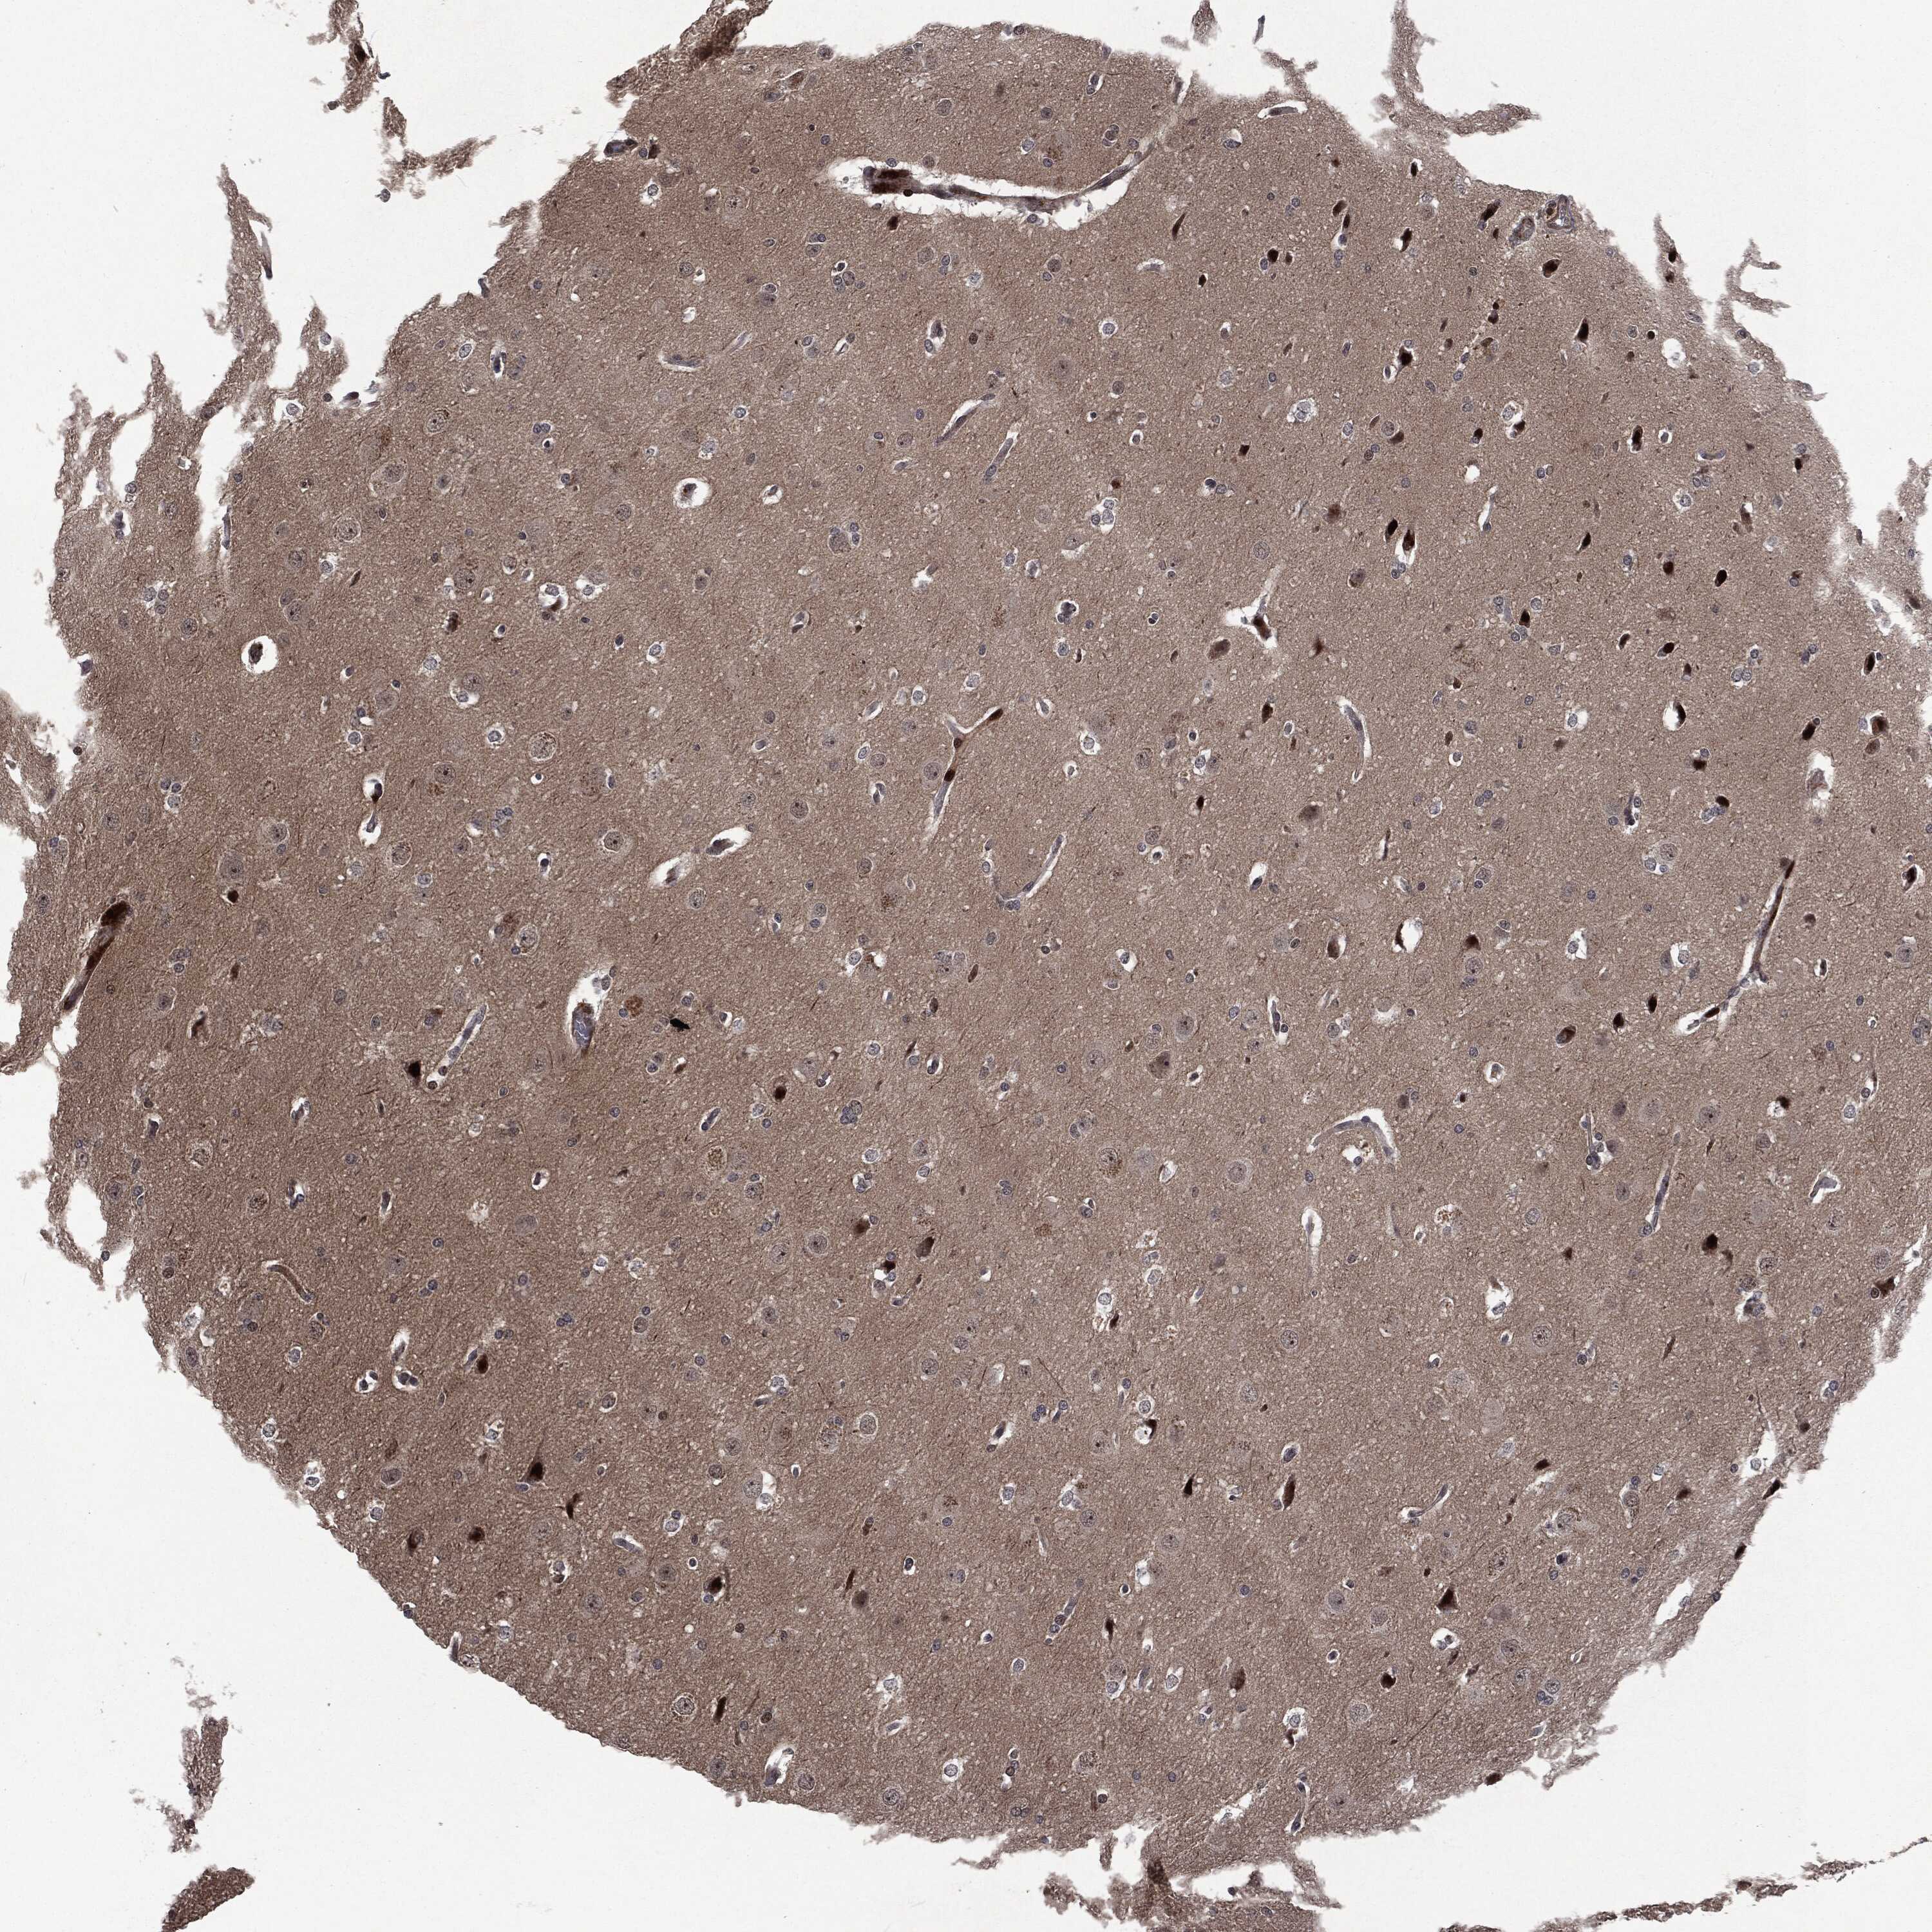

GLIOMA - Protein expressioni

A mouse-over function shows sample information and annotation data. Click on an image to view it in a full screen mode. Samples can be filtered based on level of antibody staining by selecting one or several of the following categories: high, medium, low and not detected. The assay and annotation is described here.

Note that samples used for immunohistochemistry by the Human Protein Atlas do not correspond to samples in the TCGA dataset.

Antibody stainingi

Antibody staining in the annotated cell types in the current human tissue is reported as not detected, low, medium, or high, based on conventional immunohistochemistry profiling in selected tissues. This score is based on the combination of the staining intensity and fraction of stained cells.

Each image is clickable and will lead to virtual microscopy that enables deeper exploration of all samples and also displays staining intensity scores, fraction scores and subcellular localization as well as patient and tissue information for each sample.

Glioma, malignant, High grade

Glioma, malignant, Low grade

Glioma, malignant, NOS